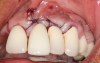

In this case, the procedure was precise, and the patient experienced minimal postoperative discomfort. An immediate postoperative digital radiograph was acquired to evaluate the radiolucent appearance of the grafted apical defect (Figure 12). After 8 weeks, the tissue appeared to be healing quickly and predictably (Figure 13), and a follow-up sagittal CBCT analysis demonstrated a new wall forming where the dehiscence had been present (Figure 14). The patient was recalled again after 5 months for radiographic analysis and intraoral evaluation, which revealed that the healing was progressing without complication (Figure 15 through Figure 18).

(13.) Follow-up 8-week postoperative photograph showing the site healing predictably.

Figure 13